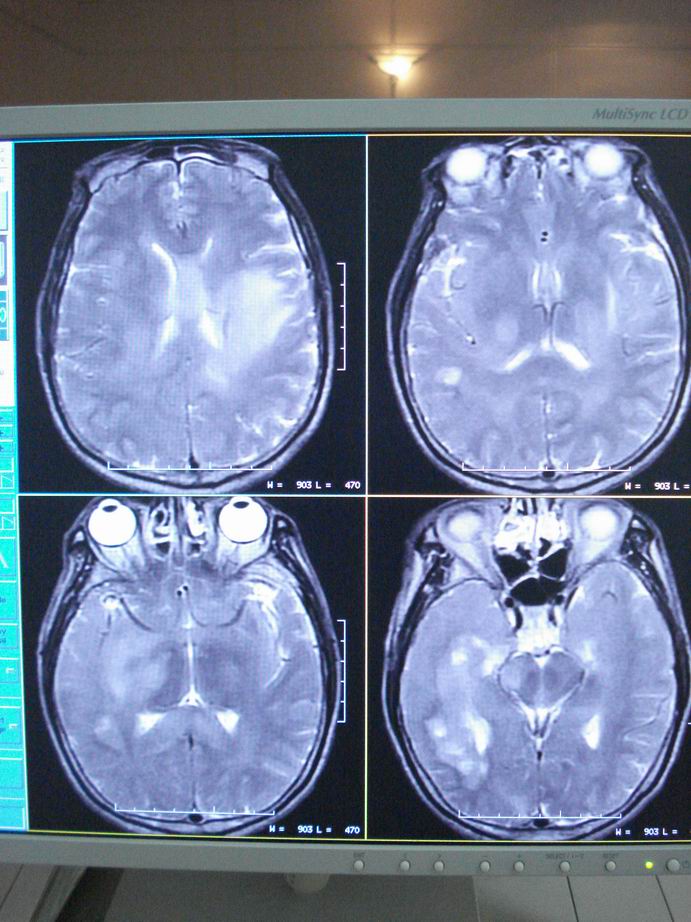

男60岁,左侧肢体乏力及精神异常10天,血压正常,血常规,肝肾功正常,腰穿无异常,请教颅内多发病灶,考虑什么?感染?肿瘤(转移性?)还是其它?

考虑为颅内多发转移瘤

脑内多发性转移瘤。

淋巴瘤较转移瘤可能大。

脑内多发占位性病变,首先考虑感染性病变,其次是转移瘤。

结合病人高龄,考虑转移瘤